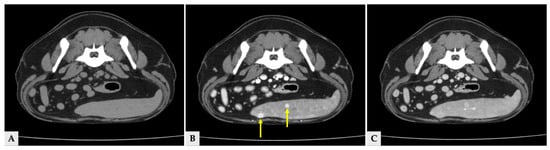

Multiple hyper- and hypoattenuating hepatic nodules were scattered throughout the liver parenchyma (maximum size 11.4 mm × 11.9 mm × 10.8 mm) (Figure 3), and numerous small splenic nodules exhibiting on pre-contrast and portal phase were also observed (Figure 4). Additionally, a soft-tissue mass was detected at the esophagogastric junction. Cervical ultrasonography revealed three distinct, heterogeneous right thyroid masses, with the largest mass demonstrating prominent vascularity on Doppler evaluation (Figure 5).

Figure 4.

Transverse CT images of splenic nodules at the same anatomical level. (A) Pre-contrast image showing splenic nodules that are isoattenuated relative to the surrounding splenic parenchyma. (B) Portal phase image at the same level demonstrating hyperattenuated splenic nodules (arrows). (C) Delayed phase image at the corresponding level, in which the splenic nodules show attenuation similar to or slightly higher than the surrounding splenic parenchyma.